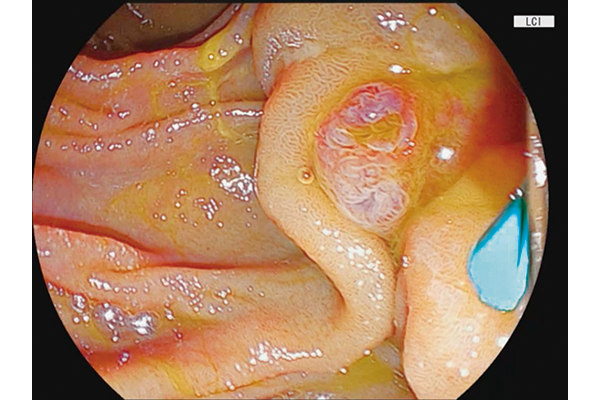

BLI,LCI and ACI technologies are incorporated.